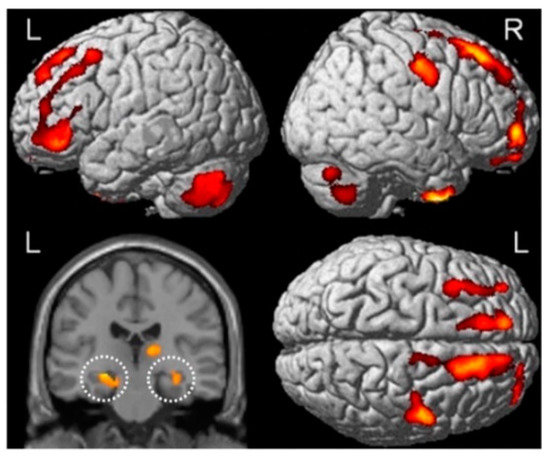

- Sekeres, M.J.; Winocur, G.; Moscovitch, M.; Anderson, J.A.E.; Pishdadian, S.; Martin Wojtowicz, J.; St-Laurent, M.; McAndrews, M.P.; Grady, C.L. Changes in Patterns of Neural Activity Underlie a Time-Dependent Transformation of Memory in Rats and Humans. Hippocampus 2018, 28, 745–764. [Google Scholar] [CrossRef] [PubMed]

- Sekeres, M.J.; Moscovitch, M.; Winocur, G.; Pishdadian, S.; Nichol, D.; Grady, C.L. Reminders Activate the Prefrontal-medial Temporal Cortex and Attenuate Forgetting of Event Memory. Hippocampus 2021, 31, 28–45. [Google Scholar] [CrossRef] [PubMed]